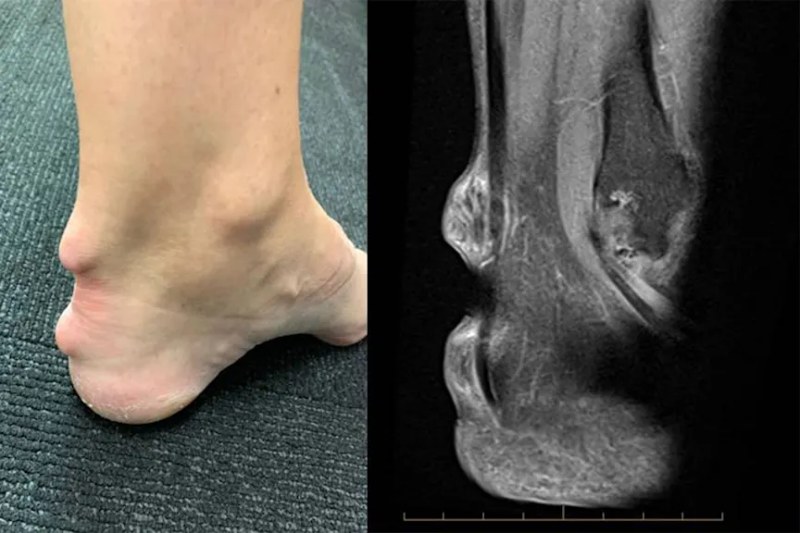

Mri nốt thấp khớp

Hình ảnh chụp MRI của một bệnh nhân gặp phải các nốt thấp khớp ở cổ chân do viêm khớp dạng thấp. Ảnh: HealthCentral

Hình ảnh mòn dọc điểm bám bao khớp

Phát hiện khớp bị mòn dọc theo điểm bám của bao khớp – dây chằng với phần thủng ở khớp vai, phì đại bao hoạt dịch khớp ở bệnh nhân viêm khớp dạng thấp. Ảnh: Radiopaedia